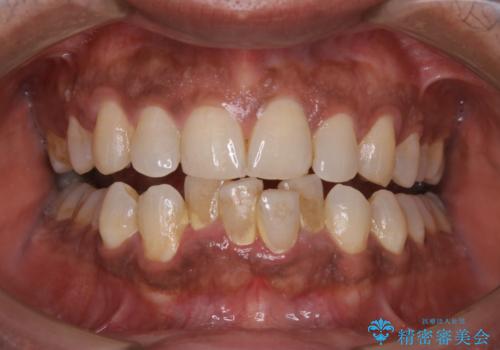

数年ぶりに歯科医院に来た 歯を綺麗にしたい

- 数年ぶりに歯科へ来院とのこと。全体的に歯のクリーニングをしてほしいとのことでした。

PMTC60分コースを行いました。

お口のトラブルを予防するには、PMTC(歯科医院で専門的な機械や材料を使用してクリーニング)を定期的に行うことが効果的な治療法です。

PMTCを行うことにより、スッキリと爽快感が得られたり、見た目も清潔感のある状態になるため、今後の治療などお口に対するモチベーションUPにも繋がります。

- 歯を白くする目的の施術ではありません